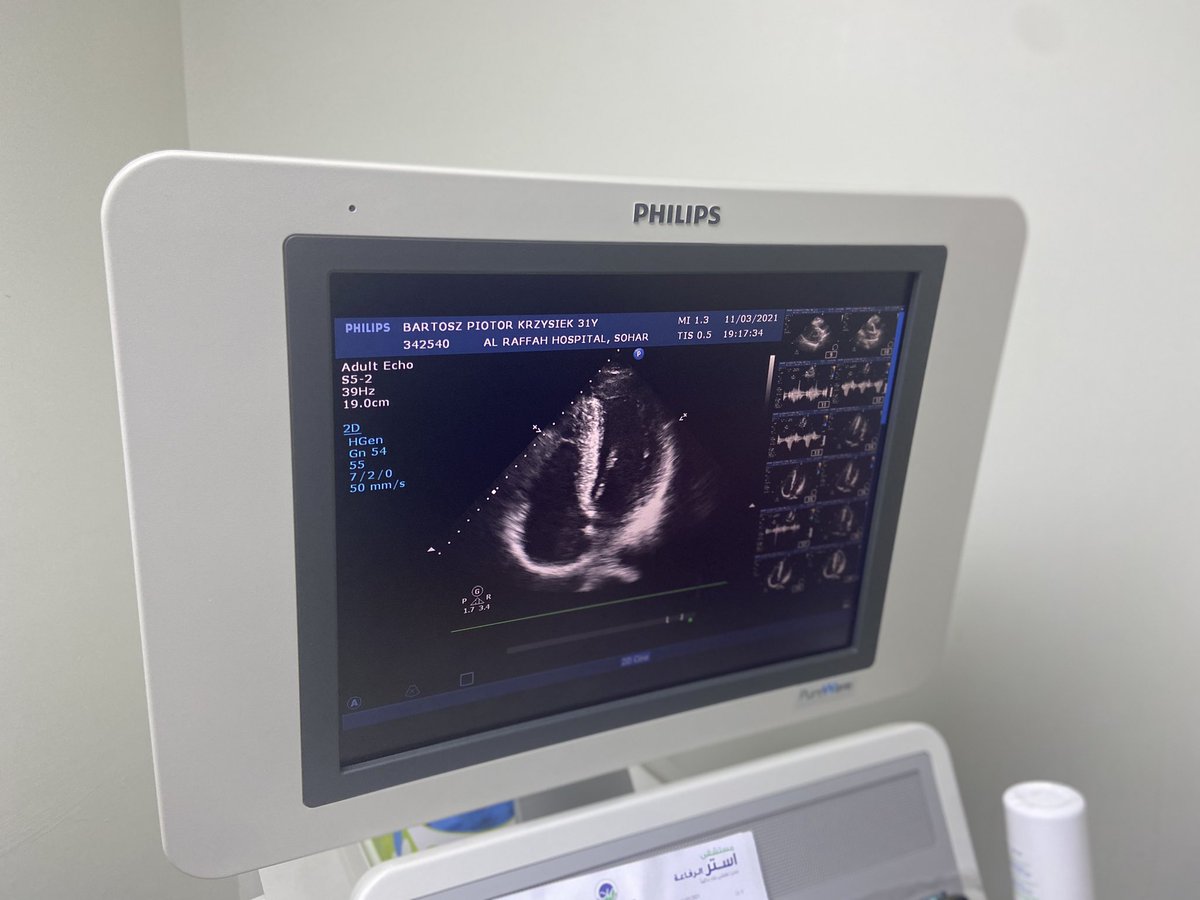

ولعل قصة اللاعبة الاولمبية Flo Hyman التي توفت في التدريب بسبب هذه الظاهرة والتي كشفتت مؤخرا بعد وفاتها انها بسبب متلازمة مارفان وتضخم الغير طبيعي في والقلب والتي توفي اخيها بسببها.. من هنا جميع الاتحادات ومراكز الطب الرياضي تجري فحوصات وظائف وهيكلة القلب مبكرا Echocardiogram 👍

المقصود بجميع الاتحادات الرياضية والمراكز بدول المتقدمة والمهتمة في هذا شأن البروتوكلات الطبية السليمة للفحوصات للرياضين في الجانب الفسيولوجي سواء كان المعملي او الاختبارات والفحوصات الطبية .. والجهاز متوفر في معظم المستشفيات الحكومية والخاصة ولكن مدي وعي الاتحادات بهذا شأن 👍